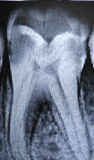

A root canal is a hollow cavity within the tooth that houses the vital part of the tooth-the pulp. The pulp provides nutrition to the tooth via the blood and is also responsible for tooth sensitivity because of the presence of the nerves.

If a canal ever gets infected, which generally occurs when tooth cavities destroys the enamel and dentin, the pulp gets exposed to the outer environment. At this stage the patient feels an intense pain that might even radiate to head and ear, sensitivity to hot and cold and discomfort. If left untreated, an infection occurs causing the death of the pulp and also infection of the surrounding bone. The stage is usually associated with the inability of the tooth to withstand chewing forces. Unless still treated, this pain will likely remain and could result in the tooth eventually falling out.

In order to prevent tooth loss, a root canal surgery must be performed. The surgery is designed to clear out diseased material from inside the canal. To perform a root canal surgery, a hole is drilled into the tooth to allow access to the inner pulp. The diseased pulp is completely removed with special instruments, and the cavity is usually filled and capped with specific inert material. |

Decayed Molar |

After RCT Filling |